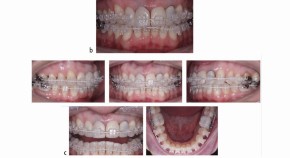

Bringing together a selection of articles from across the BDJ Portfolio, this Collection relates to the theory and practice of orthodontics. It features the BDJ Special Issue on the Orthodontic-Restorative Interface with contributions by leading national and international clinicians and researchers. Guest edited by Padhraig Fleming, it provides a contemporary, international perspective on adult orthodontics and combined orthodontic-restorative care.